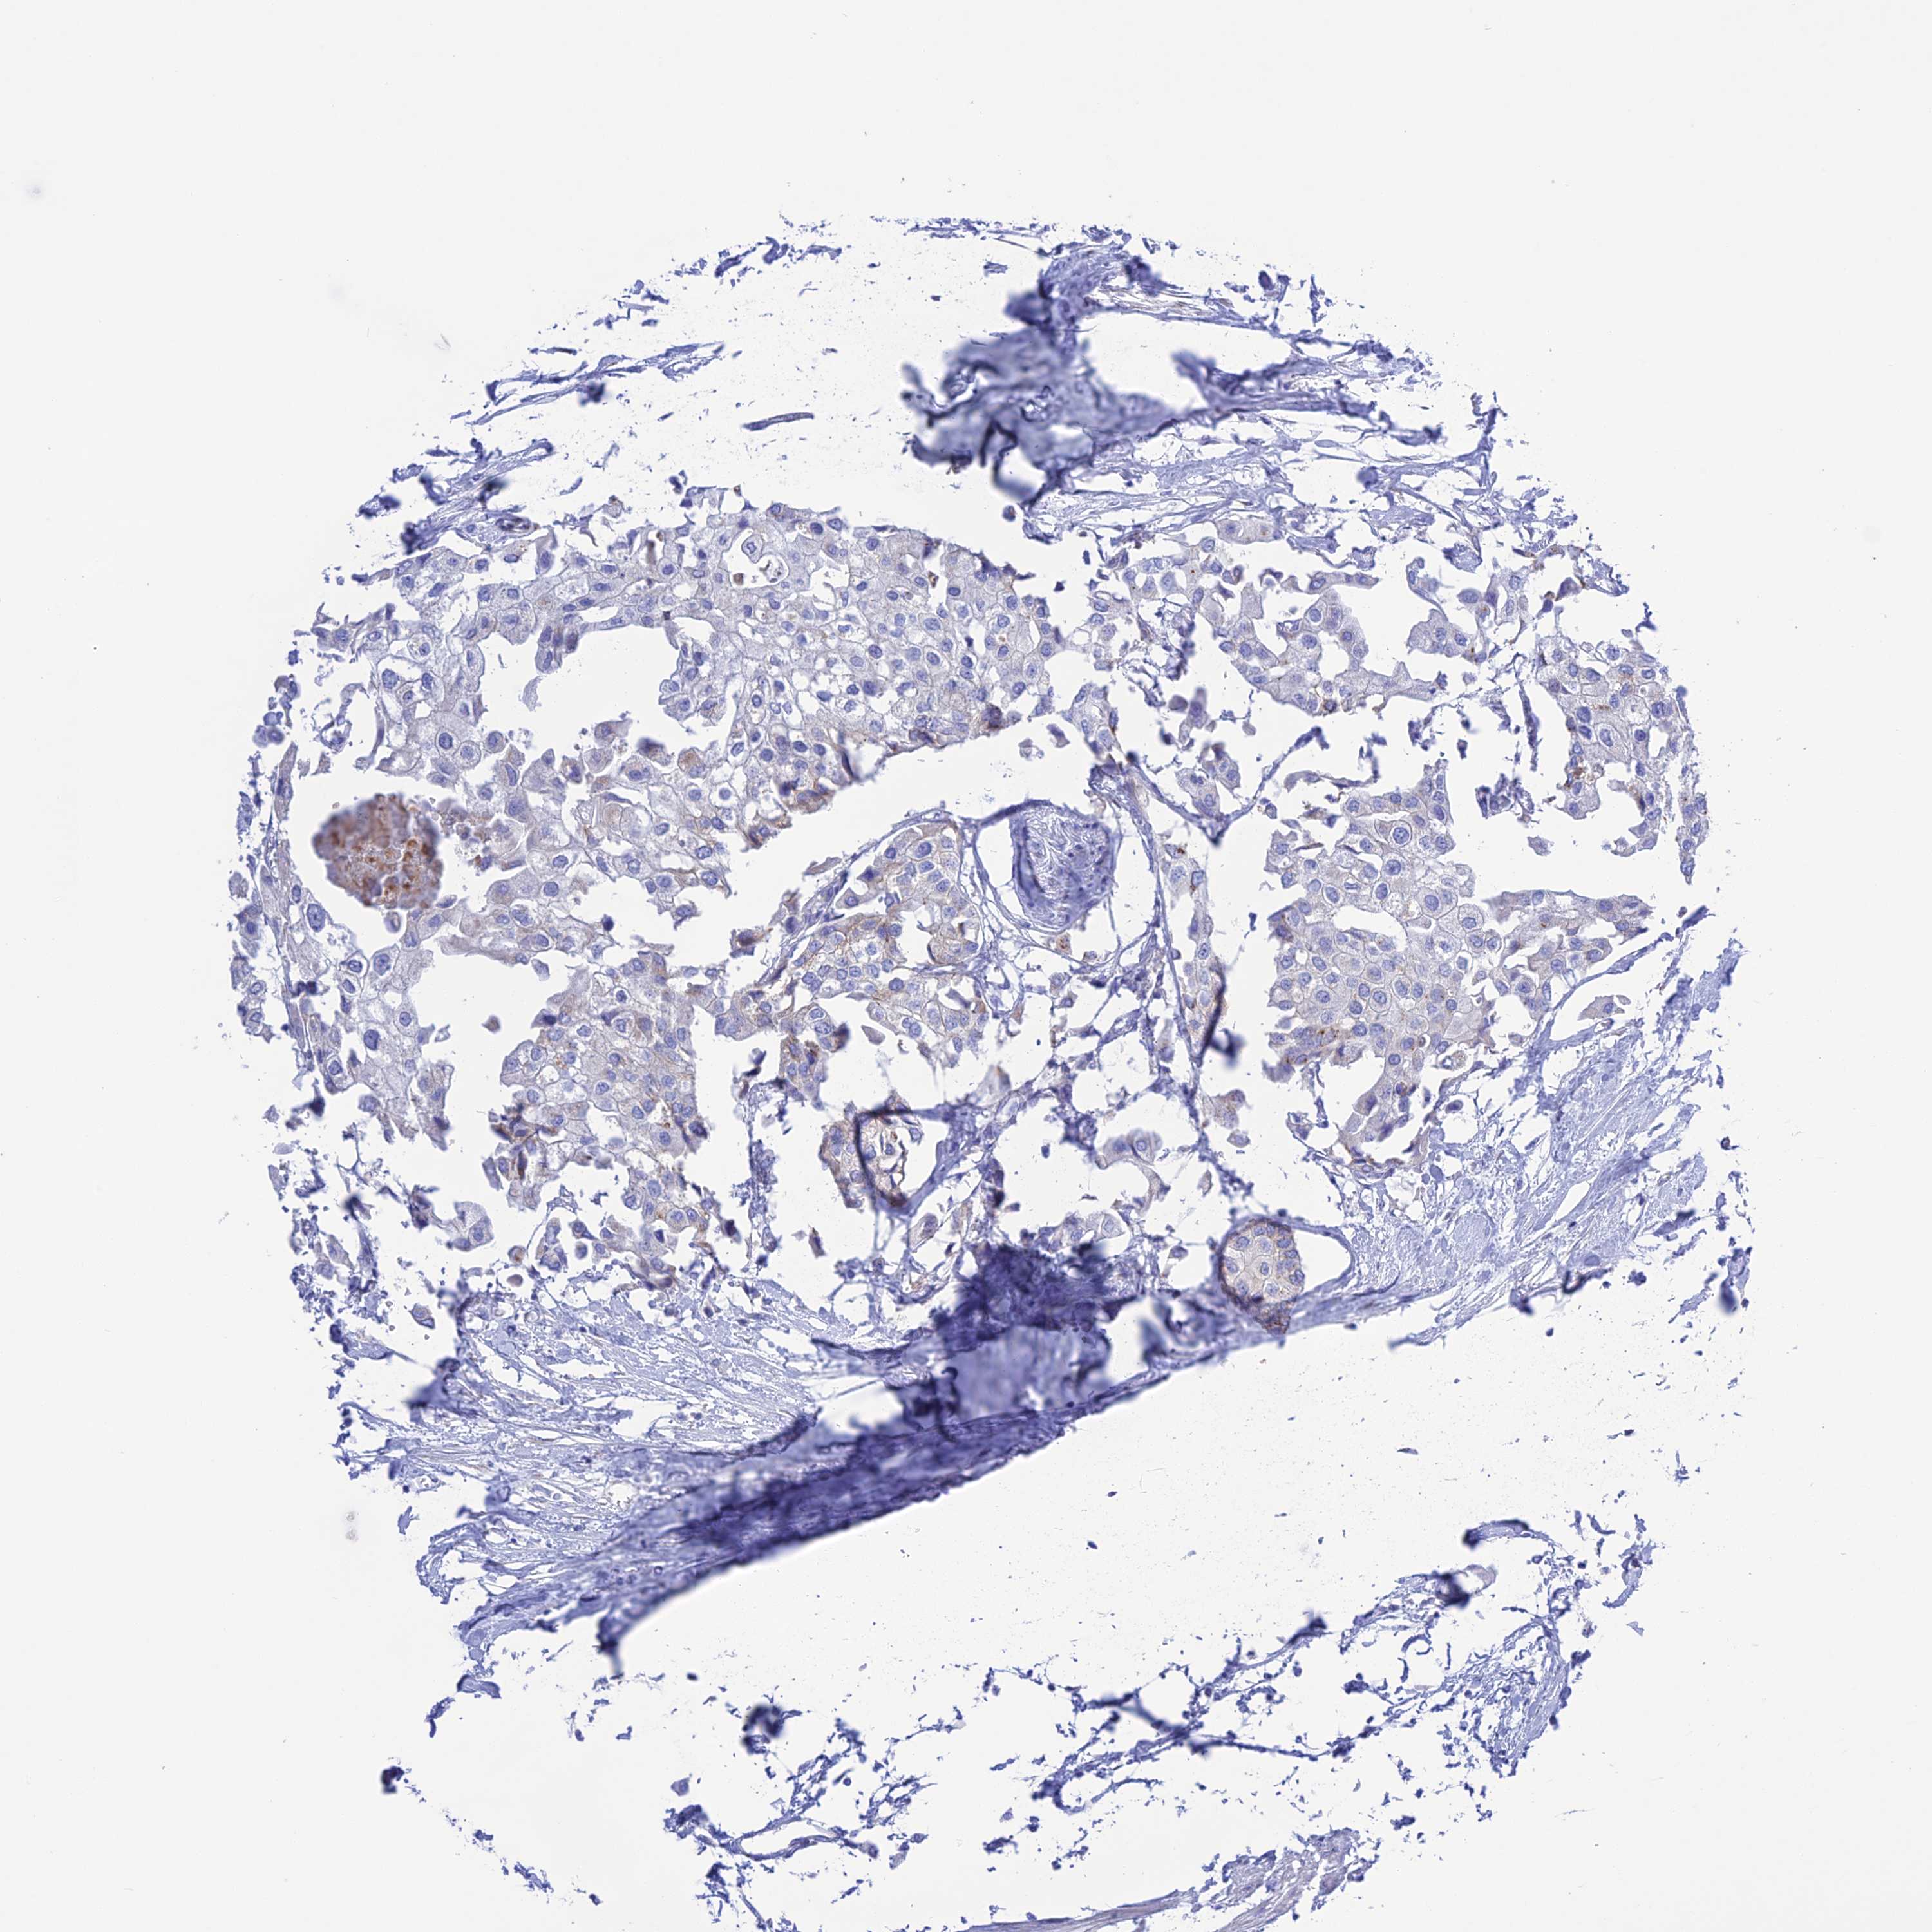

UROTHELIAL CANCER - Protein expressioni

A mouse-over function shows sample information and annotation data. Click on an image to view it in a full screen mode. Samples can be filtered based on level of antibody staining by selecting one or several of the following categories: high, medium, low and not detected. The assay and annotation is described here.

Note that samples used for immunohistochemistry by the Human Protein Atlas do not correspond to samples in the TCGA dataset.

Antibody stainingi

Antibody staining in the annotated cell types in the current human tissue is reported as not detected, low, medium, or high, based on conventional immunohistochemistry profiling in selected tissues. This score is based on the combination of the staining intensity and fraction of stained cells.

Each image is clickable and will lead to virtual microscopy that enables deeper exploration of all samples and also displays staining intensity scores, fraction scores and subcellular localization as well as patient and tissue information for each sample.

Antibody HPA044612

Staining

High

Medium

Low

Not detected

Intensity

Strong

Moderate

Weak

Negative

Quantity

>75%

75%-25%

<25%

None

Location

Nuclear

Cytoplasmic/membranous

Cytoplasmic/membranous,nuclear

Urothelial carcinoma, High grade

Urothelial carcinoma, Low grade